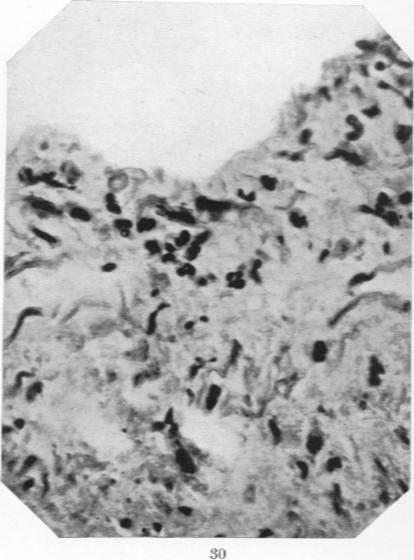

Studies in the Pathology of Rheumatic Fever: Two Cases Presenting unusual Cardiovascular Lesions.

Am J Pathol. 1927 Nov;3(6):583-594.19.